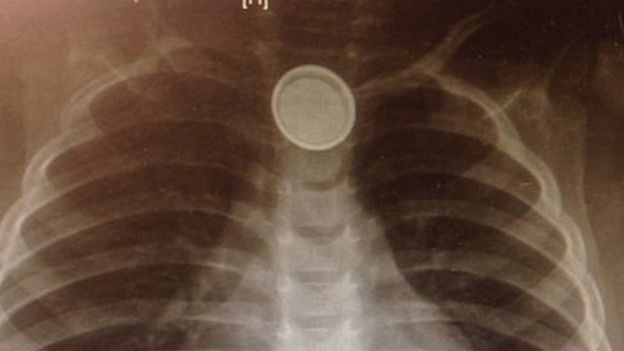

![]() |

Pin cúc áo gây tắc cổ họng bé gái |